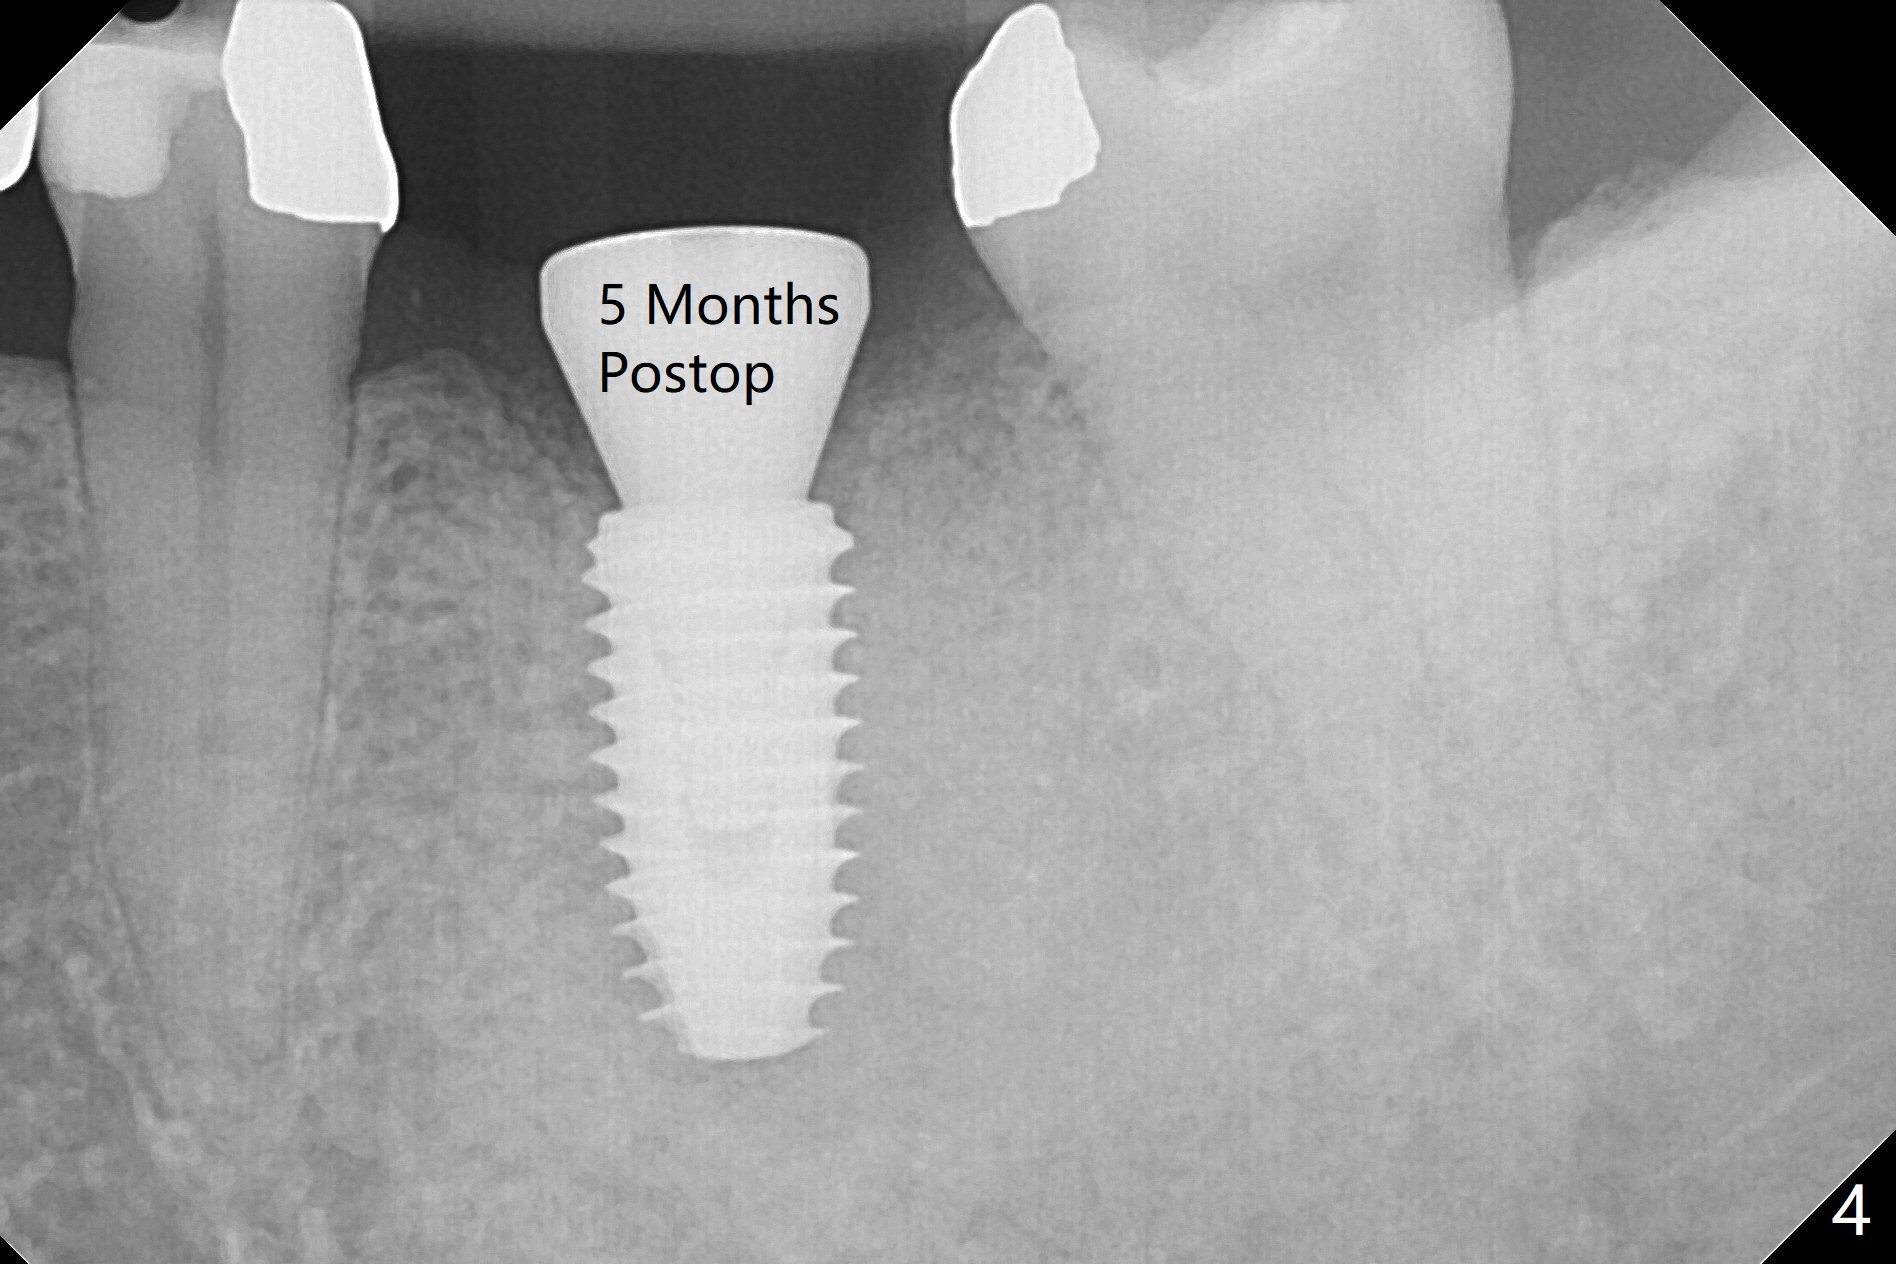

The ridge at #19 is slightly atrophic 5 months post socket preservation (Fig.1). The bone is long enough to hold a 11.5 mm long implant. There is no difficulty in inserting the corresponding drill (4.5x11.5 mm) into the metal sleeve, but the lower right posterior teeth prevent the implant handpiece from going downward completely when the handpiece accesses lingually. Because of the extra manipulation, a 5x10 mm implant achieves insertion torque of ~ 20 Ncm (Fig.2). The implant seems to be seated in the middle of the ridge (Fig.3). The bone density mesial to the implant increases 5 months postop (Fig.4), whereas that distal to the implant remains low 9 months postop (Fig.5). Bitewings taken 2.5 months post cementation (1 year postop, Fig.6,7) show subcrestal placement of the implant (advantage of guided surgery). The implant appears to be well protected; the crestal bone seems to cover the implant plateau. There will be little chance of thread exposure over years of use. The trabecular pattern around the implant is similar to that around the roots of the tooth #30 one year 7 months post cementation (2 years 4 months postop, Fig.8).